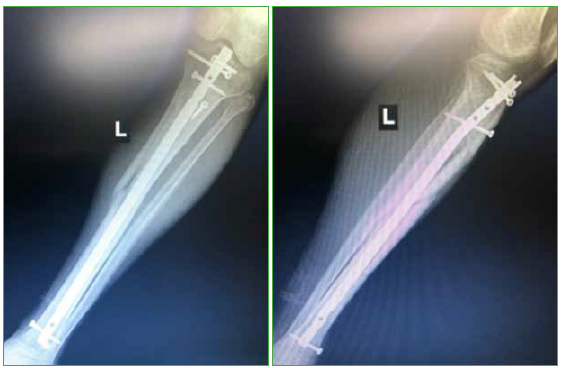

Materiales y Métodos: Se incluyó a 23 pacientes con un seguimiento posoperatorio mínimo de un año. Doce eran fracturas distales de tibia; 9, proximales y 2, segmentarias. Se evaluaron el rango de movilidad de la rodilla, el dolor posoperatorio con la escala de Lysholm, el eje posoperatorio y la tasa de consolidación.

Resultados: El arco de movilidad de la rodilla fue de 125° (rango 110-140). Al año de la cirugía, 16 de 23 pacientes no tenían dolor, 5 de 23 refirieron un leve dolor durante la actividad física y 2, dolores intensos durante la actividad física. En todos los casos, se consiguió un eje posoperatorio aceptable y la consolidación ósea. Un paciente requirió un aumento con una placa e injerto óseo.

Conclusión: La colocación de un clavo de tibia a través de un abordaje pararrotuliano medial con la rodilla en semiextensión es una técnica segura y simple para el tratamiento de las fracturas metafisarias de tibia.